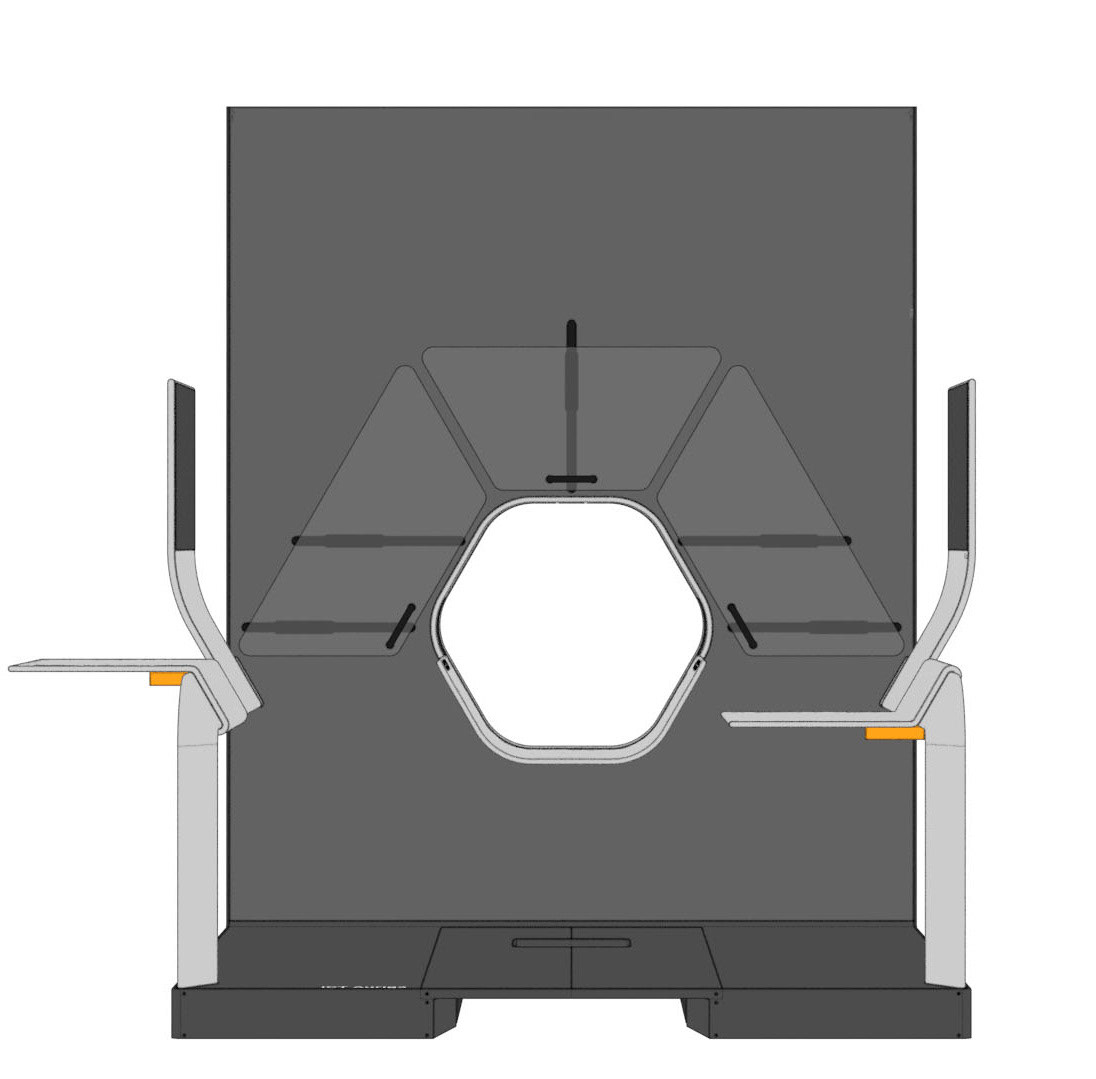

Various tables can be suspended on the railing. This enables the individual positioning of surgical instruments and devices. To relieve the interventionists, it is also possible to lean against the railing, similar to a standing seat in a gondola or tram. In addition, the railing offers protection against a potential fall from the platform.

The central design feature is the hexagonal gantry opening. It provides space for the lamps and displays. The large fronts of the gantry offer space for a display of different coloured patterns and animations, which visualize the radiation. These can be individually selected and adapted together with the overall height of the gantry. The patterns pick up on the hexagonal shape of the gantry opening and set it off. To protect the interventionists from radiation, lead glass panels and a radiation protection tray are installed. The sliding lead glass panels allow individual adaptation to the patient and the interventionists working space. The tray serves to protect the abdomen and offers a lot of foot space as well as a front leaning aid for a safe stand.

For direct inspection of the CT scans, there is one large overview screen per side and a small detail screen inside the gantry. The control interface of the gantry is located inside the lower trough, which protects the abdomen of the interventionists from radiation. In addition, there is a foot pedal on the floor that allows hands-free activation of the CT imaging.